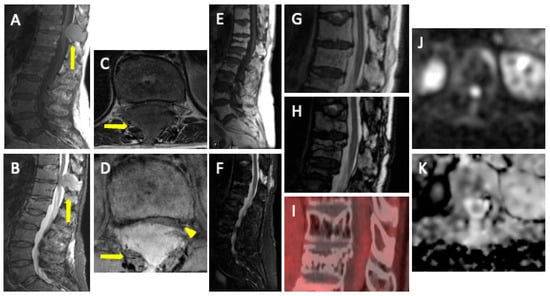

4. WBMRI

4.2. Disease Patterns

- Apparently normal bone marrow.

- Focal pattern: Focal myeloma infiltration was defined by circumscribed areas of high SI on STIR and T2WI. These corresponded to areas of low SI or, in a few cases, isointense signal upon an unenhanced T1WI [31]. The definition of focal lesion has evolved lately through the use of sequences such as DWI and Dixon. Therefore, focal lesions are defined as lesions greater than 5 mm hyperintense to background muscle at a b-value of 900 s/mm2, using ADC maps and confirming these findings with the corresponding Dixon sequences [32].

- Micronodular pattern: The micronodular or variegated or “salt and pepper” pattern presents a widespread heterogeneity with tiny nodular areas of altered diffusion signal (<5 mm) and T1WI hypointensities with preserved normal marrow between them [26].

- Diffuse pattern: Diffuse disease can be suspected from a diffuse decreased signal on T1WI (either iso- or hypointense to intervertebral discs and muscle) and a diffuse increased signal throughout the marrow on T2FSWI, STIR, or high b-value DWI. Marrow ADC values above 600–700 μm2/s in a nontreated and newly diagnosed patient with MM could be used to increase confidence for the diagnosis of diffuse marrow involvement [33] (Figure 7). Due to potential false-positive findings, diffuse disease in imaging must be supported by bone marrow trephine biopsy [26].

- Mixed pattern: This pattern combines diffuse and focal patterns.

4.3. Follow-Up Imaging Features